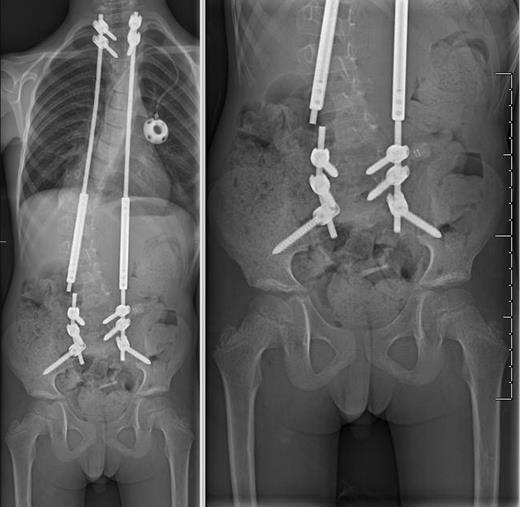

One month after completing radiation (3 years since diagnosis), he reported increasing back pain along with failure to thrive and resultant difficulty attending school. Plain films demonstrated continued relative stability of his curvature at 44 degrees, and his increased back pain was attributed to early toxicity from radiation. Over the following 2 months, his back pain continued to progress, he also complained of neck pain and his mom noted subjective worsening of his curve. His narcotic requirement had increased, and imaging confirmed worsening of his thoracolumbar scoliosis with his curve measuring 64 degrees (Figs 2B and 3A). At this point, we recommended surgical intervention with placement of dual growth rods given the significant curve progression and deterioration in functional status (McCormick Grade III).

Anterior-posterior (AP) plain films of the spine at the time of diagnosis (A), after curve progression (B) and 1 year after growing rod insertion (C). Measured Cobb angles were 32 degrees (A), 64 degrees (B) and 22 degrees (C), respectively.

We placed dual growth rods from T2 to the ilium with a posterior spinal fusion from T2 to T3 and L5 to the ilium. The surgical technique has been previously described in detail by Akbarnia et al. [7]. Motor evoked potentials and somatosensory evoked potentials remained stable throughout the entirety of the case. Postoperatively, he had full strength.

He had three total lengthening procedures in the first 14 months since placement of the growing rods with improvement in his scoliotic curvature to 22 degrees (Figs 2C and 3B). Eighteen months after insertion of his growing rod construct, he developed hardware infection requiring hardware removal. He is scheduled to undergo definitive fusion in the near future. He has returned to his initial independent functional status with minimal gait abnormality (McCormick Grade II) and is able to participate in activities such as biking and skateboarding. He is now 10 years old.